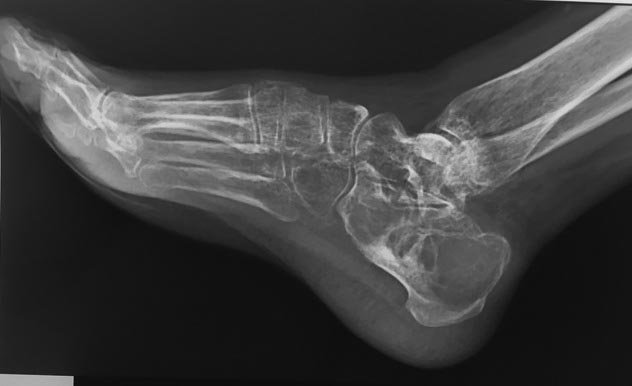

Пациентка Г., 38 лет. 1,5 года назад появились боли в левой пяточной кости.

Болей в покое и ночных болей нет. 08.09.15 операция: экскохлаеция аневризмальной костной кисты, пластика деминерализованными костными трансплантатами. По данным МРТ (29.02.16) костной перестройки нет, вероятно произошел выход содержимого кисты в пространство позади ахиллова сухожилия. Планируется проведение РКТ, биопсии. Вопрос: чем можно заполнить ? Костный цемент? Или снова деминерализованные костные трансплантаты?

Почему у пациентки кости столь рентгенпрозрачные? Почему такой вот остеопороз?

После операции пациентка ходит с костылями без нагрузки на ногу. С этим связан остеопороз.

Остеопороз судя по рентгенограмме был до операции. Нужно исключить гиперпаратиреоз -болезнь Реклингаузена.

У пациентки на первой рентгенограмме угол Беллера нулевой.

Был ли патологический перелом?

Такой угол Бэлера мог сформироваться из-за деформации, выбухания кости, развившаяся из-за высокого внутрикситозного давления.

Привет всем!По снимкам угол Беллера 0 значит были патологические переломы или все так разьело и просела подтаранная площадка пятки,если нет перестроики транспланта скорее онко или какая то система.Все прооперированные кисты аневризмальные пятки с аутокостью перестроились полностью в сроки примерно 6-8месяцев.